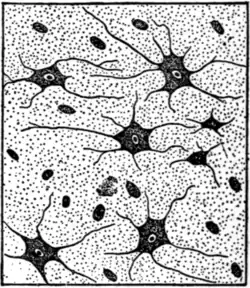

Fig. 18.—Diagram drawn from photomicrograph to show different forms of neuroglia cells in a patch of sclerosis secondary to degeneration and disappearance of the neurones. Observe the large branched cells of Deiters.